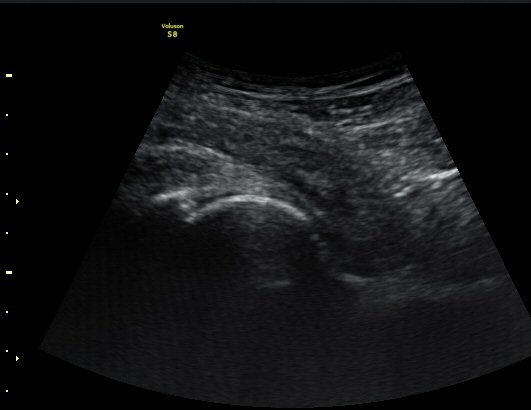

ŽÃËÀÚ¸¦ ¾ûµ¢ÀÌ °üÀý ¿ÜÃø Á¾´Ü¸é°Ë»ç ½Ã ÀüÇÏÀ屨(AIIS)¿¡¼­ ¼®È¸È­¼º À½¿µÀÌ °üÂûµÊ(»çÁø 2, 3).

¼±»óŽÃÊÀÚ¸¦ ÀÌ¿ëÇÑ °Ë»ç¿¡¼­ ÀüÇÏÀ屨ÀÇ ´ëÅðÁ÷±Ù ±â½ÃºÎ¿¡ ¼®È¸È­ À½¿µÀÌ ¶Ñ·ÈÈ÷

°üÂûµÊ(»çÁø 4, 5).